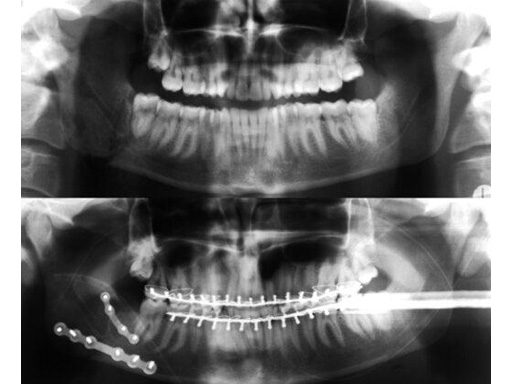

Pre- and postoperative x-rays of a right mandibular angle fracture treated with two 2.0 mm Mandible Locking Plates (mini and extra).